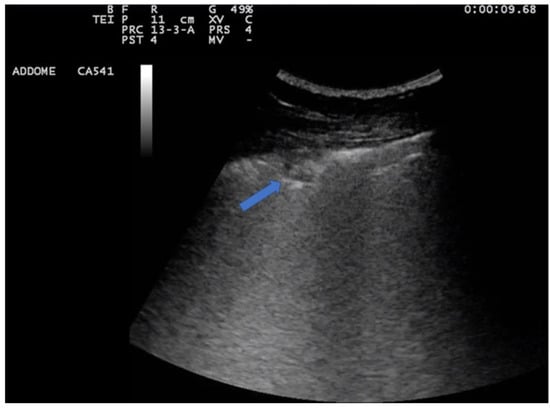

3. Lung Ultrasound Evaluation

4. Lung Ultrasound on Physiological Lung